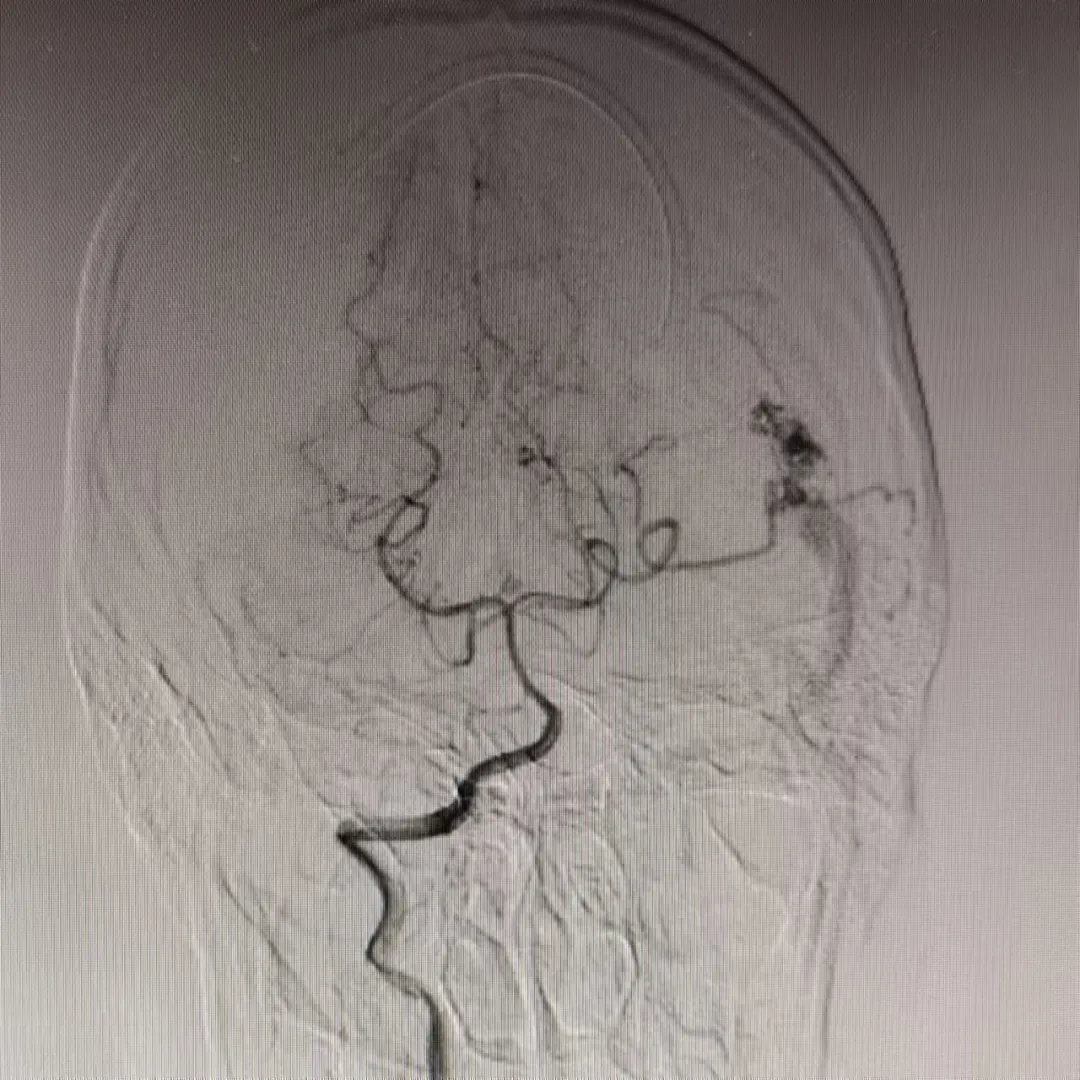

“叮鈴鈴,叮鈴鈴......”。凌晨一點,滄州市中心醫(yī)院神經(jīng)血管介入二科姜紅升醫(yī)生睡夢中被一陣急促的電話鈴聲吵醒,電話是某地縣醫(yī)院醫(yī)生打來的:一位高考完畢的18歲姑娘于夜間突然出現(xiàn)劇烈頭痛,伴惡心、嘔吐,隨后意識不清。這位患者被家屬送至當?shù)蒯t(yī)院,急查頭顱CT(圖一)示:左側(cè)顳枕葉腦出血破入腦室系統(tǒng),蛛網(wǎng)膜下腔出血。當?shù)蒯t(yī)院醫(yī)生隨即電話聯(lián)系姜紅升醫(yī)生并簡要說明了患者的基本情況。姜醫(yī)生了解相關情況后,依據(jù)患者為青年女性,既往體健,查體情況以及影像學結果提示,考慮腦動靜脈畸形破裂出血可能性大。姜紅升醫(yī)生、當?shù)蒯t(yī)院醫(yī)生同患者家屬緊急商議,最后家屬決定將患者轉(zhuǎn)至滄州市中心醫(yī)院腦科院區(qū)繼續(xù)治療?;颊咿D(zhuǎn)入滄州市中心醫(yī)院后完善查體:意識不清,精神差,反應遲鈍,刺痛可發(fā)音,雙側(cè)瞳孔正大等圓,對光反射遲鈍,頸項強直,刺痛四肢可動,巴氏征(-)。為預防腦疝形成,醫(yī)生們緊急對患者行“腦室外穿刺引流術”。 姜紅升醫(yī)生考慮,腦血管畸形出血情況不明下貿(mào)然手術可能會出現(xiàn)術中大出血、腦腫脹、畸形團位置不明確等嚴重后果,并且腦血管畸形存在著再次破裂出血、癲癇等可能性。遂向患者家屬交待行腦血管造影及視情況行介入治療的必要性?;颊呒覍俦硎局槔斫?,并同意造影及后續(xù)介入治療操作。姜紅升醫(yī)生遂于當日上午對患者行腦血管造影檢查。 患者造影結果提示:左側(cè)顳枕部動靜脈畸形,左側(cè)大腦后動脈顳后動脈分支主要供血,左側(cè)大腦中動脈少量供血,畸形團約2cm,通過橫竇引流。 了解造影結果后,姜紅升醫(yī)生與科室各位醫(yī)生對適合患者的治療方式進行討論:外科手術是當前治療腦血管畸形的主要方法,其優(yōu)勢在于根除病變部位,避免再次復發(fā);但手術前需要仔細研讀影像資料,了解畸形血管團生長的位置、大小、是否位于功能區(qū)、正確識別主要的供血動脈和引流靜脈等等,評估術中大出血、惡性腦腫脹、術后神經(jīng)系統(tǒng)功能缺損的風險,對手術方案的制訂和實施至關重要。介入治療創(chuàng)傷小,對于處理深部、功能區(qū)等手術無法切除的腦動靜脈畸形具有明顯優(yōu)勢;但介入治療相較于外科手術亦存在諸多不足:如不能達到治愈性栓塞,因改變畸形血管團的血流動力學,反而增加再次破裂出血的風險;栓塞材料的移位亦可能導致正常血管的閉塞,引發(fā)神經(jīng)功能障礙;以及介入治療后術后存在高復發(fā)率等等。本例患者畸形血管團位于非功能區(qū),其體積較小,合并顱內(nèi)出血,擬為患者行“介入栓塞+外科手術切除”治療策略:首先對腦血管畸形團供血動脈進行栓塞,降低畸形血管團血流量,從而大大降低后續(xù)外科手術切除過程中發(fā)生出血、腦腫脹的風險,提高外科手術的安全性,然后再對患者進行外科手術治療,達到根除病灶的效果。制訂出該患者治療策略后,姜紅升醫(yī)生對患者家屬充分交待病情以及手術方案,得到家屬的理解與同意。 團隊遂于介入導管手術臺上開始對患者畸形血管團進行介入栓塞,經(jīng)Marathons微導管向主要供血動脈及畸形血管團,分次注入Onyx膠。再次造影,提示畸形血管團殘余少量顯影,主要供血動脈消失,余血管未見異常。 栓塞術后待患者略恢復后,完善磁共振掃描等相關檢查,嚴密制訂手術計劃,于數(shù)天后行“腦血管畸形切除術”。顯微鏡下熒光造影,識別主要引流靜脈,確認后保護好引流靜脈,沿畸形血管團切除及清除顱內(nèi)出血,待完整切除動靜脈畸形團后,將引流靜脈電凝切斷。術后給予患者對癥治療,經(jīng)過積極治療,患者恢復良好,未遺留明顯后遺癥,順利出院。 在患者出院后,姜紅升醫(yī)生也收到了該患者被大學錄取的喜訊。出院后的患者即將迎來嶄新美好的大學生涯。 溫馨提示 年輕、既往無高血壓病史患者,如出現(xiàn)腦出血,務必考慮到腦血管畸形的可能性,盡量爭取機會完善相關檢查,確定患者腦出血的病因,并根據(jù)患者實際情況,嚴密制訂合理的治療策略。如貿(mào)然為患者行顱內(nèi)血腫清除術,可能會導致術中大出血,惡性腦腫脹等惡性事件,導致患者出現(xiàn)致死致殘的災難性后果。